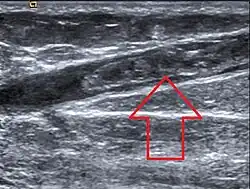

Thrombus in Vena saphena magna

Die Diagnose einer Venenthrombose wird heute üblicherweise mittels Sonographie (Doppler- und Duplex-Sonographie) gestellt. Falls dieser nicht vorhanden ist oder nach der Ultraschalluntersuchung weiter Unklarheiten über das weitere Vorgehen bestehen, kommt die Phlebographie (Röntgenuntersuchung mit Kontrastmittel) zur Anwendung. Ist ein modernes Ultraschallgerät vorhanden und ist der Untersucher ausreichend erfahren, muss die aufwändigere und den Patienten belastendere Phlebographie nur noch selten zum Einsatz kommen.